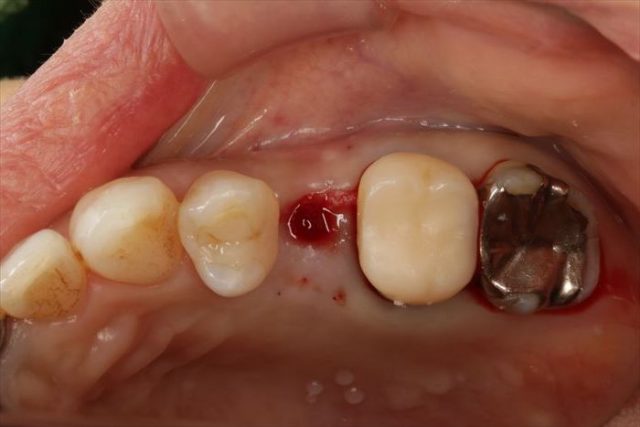

本日いよいよインプラント埋入オペに臨みます。

前後の歯も今後治療を進めていきますが、まだ手つかずの状態です。

この部分は抜歯とメタルタトゥーの切除を行った場所です。